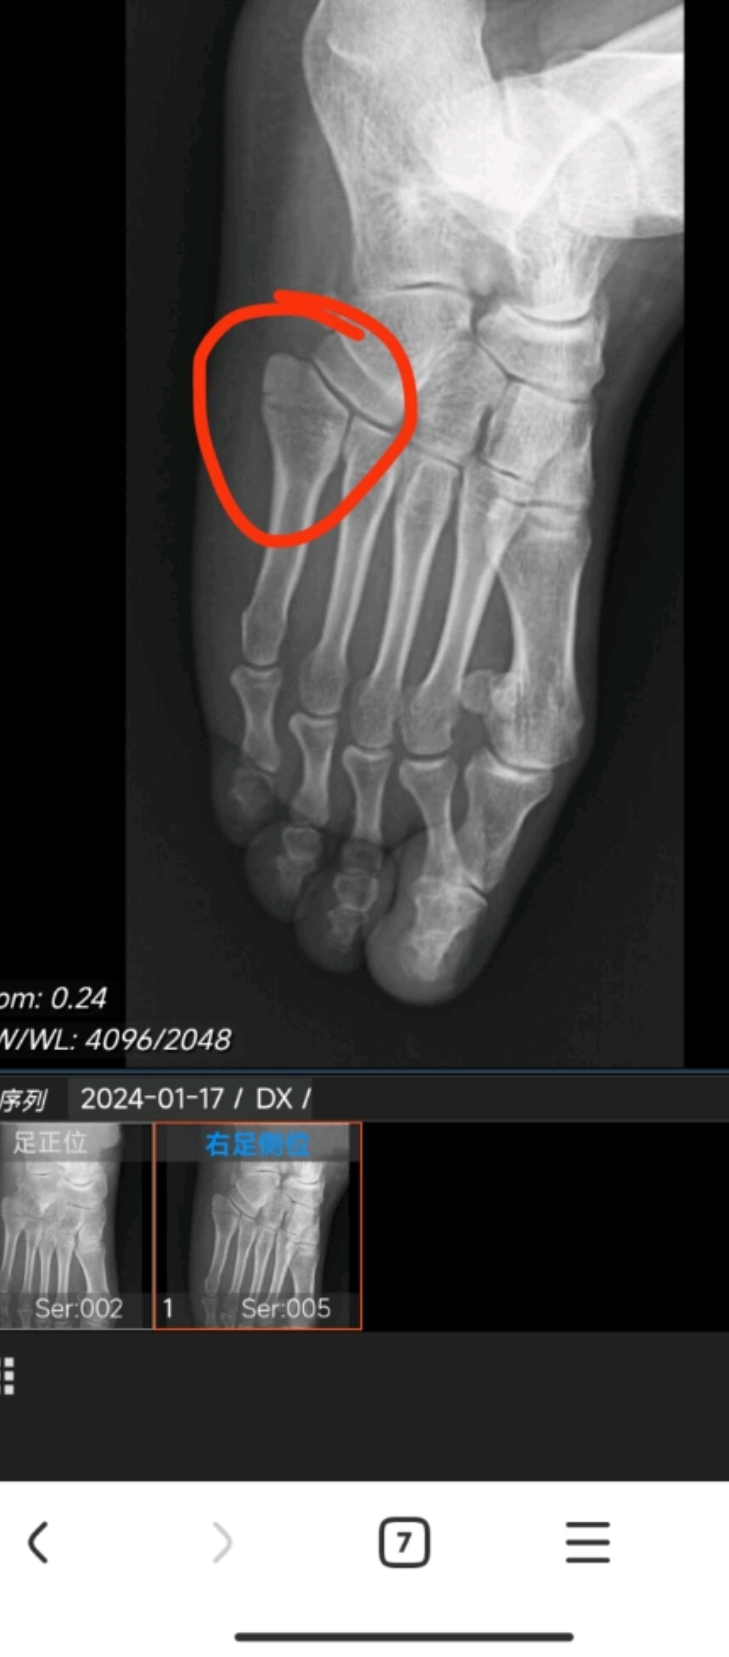

Lisfranc损伤是什么?如何治疗?